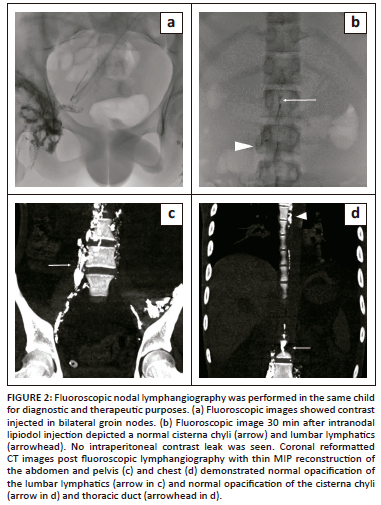

Nodal fluoroscopic lymphangiography was also performed for the patient a few days after the MRI study. Following the administration of lipiodol through the inguinal nodes, multiple spot images were obtained of the pelvic and retroperitoneal lymphatics (Figure 2a and b). No free spill was seen in the abdominal cavity. Post-procedural CT also revealed normal anatomy of the centrally conducting lymphatic channels without contrast extravasation (Figure 2c and d).

The likely site for the lymphatic leak was attributed to the distal intestinal lymphatic channels without any injury to the central conducting lymphatics. The patient proceeded to surgery and underwent lipiodol injection into the mesenteric lymph nodes. Following surgery, the drain output gradually reduced, and the patient showed clinical improvement.

Imaging of the lymphatic system has been difficult due to the complex nature and small size of the lymphatics.5 Earlier, fluoroscopic lymphangiography techniques using ethiodol-based contrast agents were used for both diagnostic and therapeutic purposes. However, the relationship of the lymphatic duct with adjacent structures cannot be delineated, thus limiting the role of fluoroscopic-guided lymphangiographic techniques to therapeutic interventions. More recently, the use of DCE-MR lymphangiography with gadolinium-based contrast agents helps overcome the limitations of fluoroscopic techniques.

In the first case, there was no evidence of injury to the cisterna chyli or thoracic duct on MR lymphangiography. As a result, surgery was performed and embolising agents were injected into the mesenteric nodes to target the distal intestinal lymphatics. In the second case there was non-opacification of the CCLs cranial to the renal hilum due to compression by enlarged abdominal lymph nodes. The patient was commenced on anti-tuberculous therapy with close monitoring and there was a gradual reduction in chylous output.